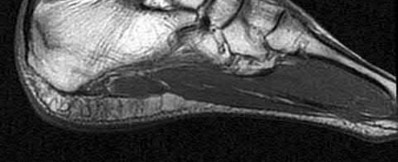

Figure 28 is the lateral radiograph of a patient who sustained an intra-articular fracture of the calcaneus. The structure (*) depicted by the arrows most likely represents which osseous component of the calcaneus?

Lateral portion of the posterior facet Corrent answer: 5

Fractures of the calcaneus occur as a result of shear and compression forces. Foot position at the time of impact, the force of the impact, and bone quality all dictate the degree of comminution and fracture line orientation. Two primary fracture lines are consistently observed, one of which divides the calcaneus into medial and lateral portions. An essential feature of this fracture

line is that it creates a fragment (sustentaculum tali) that remains attached to the talus by the interosseous ligament. This medial portion (constant fragment) of the posterior facet retains its normal anatomic position beneath the posterior talus. Its corresponding lateral component (labeled with an * in the figure), however, can be found displaced inferiorly within the body of the calcaneus. It is often rotated 90 degrees (as depicted in Figure 28) in relation to the remainder of the subtalar joint. This gives the appearance of what has been described as the "double-density" sign. The middle facet is more anterior and less commonly displaced. The lateral wall is nonarticular.